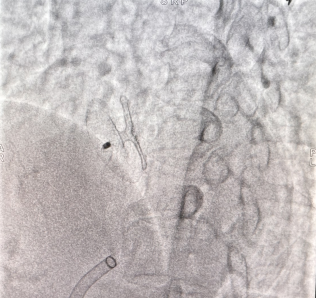

Case 1

卵圆未闭合并房间隔膨出瘤。卵圆孔隧道长度4.9mm,裂隙直径1.4mm,房间隔膨出瘤基底宽21mm,深度约9mm,可见左向右分流。应用D-shufo 3036-6 PFO封堵器成功封堵。